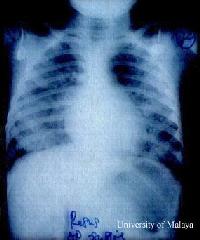

Deaths of Children during an Outbreak of Hand, Foot,

and Mouth Disease in Sarawak, Malaysia: Clinical and

Pathological Characteristics of the Disease. Clin Infect Dis. 2000 Sep;31(3):678-683.Chan

LG, Parashar UD, Lye MS, Ong FG, Zaki SR, Alexander JP,

Ho KK, Han LL, Pallansch MA, Suleiman AB, Jegathesan M,

Anderson LJ. [MEDLINE

abstract]